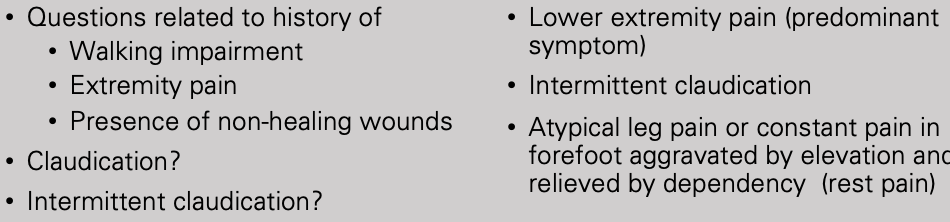

What does this refer to

Progressive severity

asymptomatic

intermittent claudication

pain at rest

nonhealing wounds

ulceration

gangrene and threatened limb

Clinical history of Peripheral Artery Disease (PAD)

What does this refer to

Physical exam peripheral artery disease (PAD)